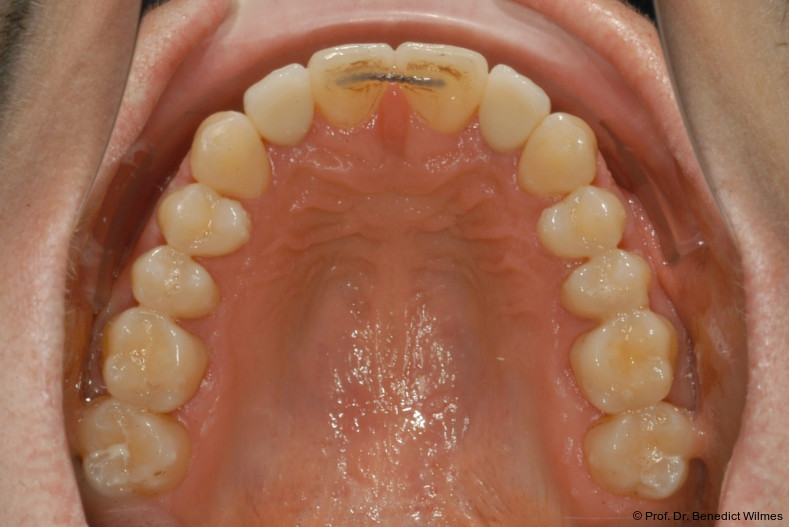

Ein 14-jähriger Patient wurde bei Aplasie der beiden oberen seitlichen Schneidezähne mit dem Ziel der beidseitigen Lückenöffnung kieferorthopädisch therapiert (Abb. 1a+b). Zum Ende der kieferorthopädischen Behandlung wurden zwei Miniimplantate in Regio 2er als temporärer Zahnersatz inseriert (Benefit System, PSM, 2 x 13 mm, Abb. 2a+b). Nach Abdrucknahme wurden Kronen auf den Peek-Abutments modelliert und diese mit Kunststoff auf die Abutments geklebt (Abb. 3a–d). In den Abbildungen 3 und 4 sind die klinischen und röntgenologischen Nachkontrollen innerhalb der nächsten achteinhalb Jahre dokumentiert. Man erkennt einen sowohl in der Höhe als auch in bukkopalatinalen Breite verbleibenden gesunden Knochen ohne Anzeichen einer Atrophie. Im Alter von 23 Jahren wurden die definitiven Implantate ohne die Notwendigkeit einer Augmentation eingesetzt (Abb. 5) und nach Einheilung prothetisch versorgt (Abb. 6a–e und Abb. 7a–c).

Nach Abschluss der kieferorthopädischen Pfeilerverteilung wurden zwei Miniimplantate in Regio 3er inseriert (2 x 13 mm). Nach Herstellung im Labor wurden Kronen auf den Miniimplantaten aufgeschraubt (Abb. 13+16a–d). Auch hier wurde darauf geachtet, dass die Kronen aus der Okklusion geschliffen wurden (Abb. 14). Bei den Nachkontrollen zeigten sich ebenfalls stabile Miniimplantate und ein entzündungsfreies Implantatlager ohne erkennbare Atrophie des Knochens (Abb. 15 und 16a–d).